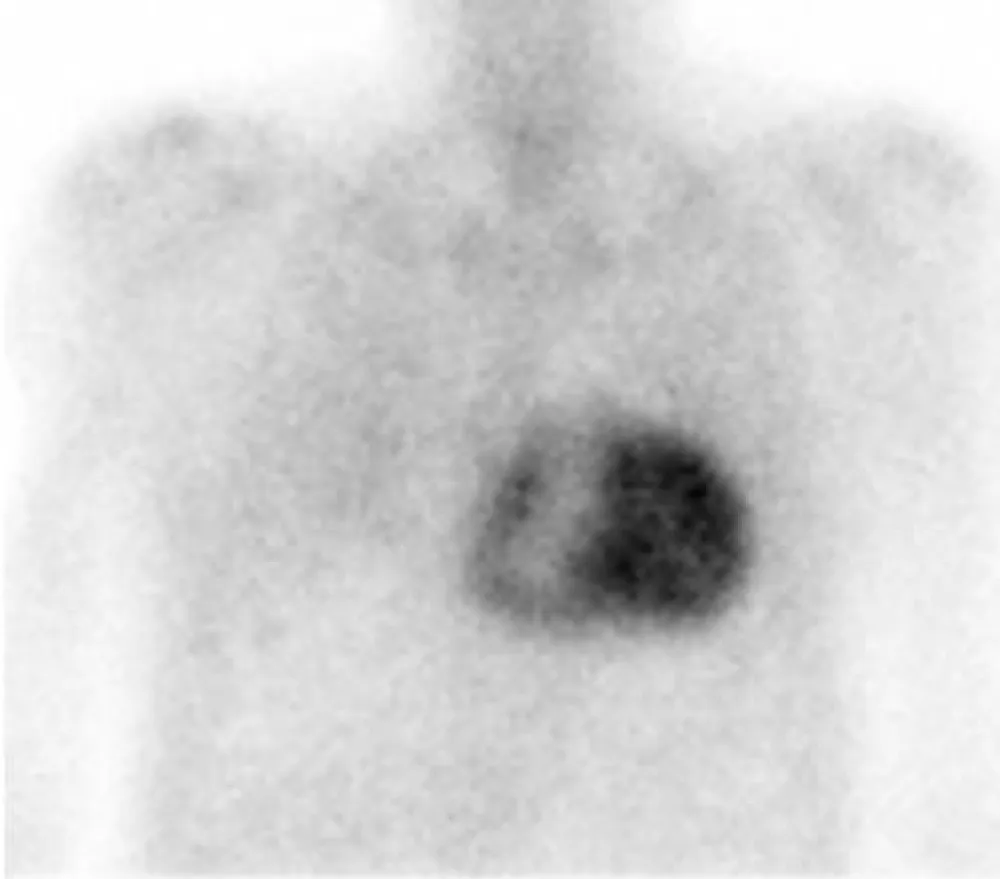

In order to identify the origin of amyloidosis, a Tc99m-DPD scan was requested, after obtaining written patient informed consent, a planar whole-body scintigraphy was performed 2 hours after intravenous injection of 740 MBq, that showed intense biventricular myocardial tracer uptake grade 3 (greater than the bone uptake), compatible with cardiac TTR amyloidosis, (Figures 1,2). Finally, a Genetic Testing resulted negative for TTR gene Mutation, which is consistent with the diagnosis of cardiac amyloidosis ATTRwt.

Figure 1: Anterior and posterior views whole body 99mTc-DPD scan. Marked myocardial uptake, suggesting an amyloid infiltration.

Figure 2: 99mTc-DPD anterior planar image show intense biventricular myocardial uptake (grade 3).

Bone tracer scintigraphy, using 99mTc-DPD, 99mTC-HMDP, and 99mTc-PYP, has been employed as a diagnostic test for ATTR. It is proven to be more than 99% sensitive for grades 1, 2, and 3 (the grading visual score, considers the myocardial tracer uptake compared with the bone uptake: grades 1 less than the bone uptake, grade 2 equal to the bone uptake and grade 3 greater than the bone uptake), and 97% specific for ATTR amyloid in the presence of grade 2 or 3 cardiac uptake [11]. It should be carried out under clinical suspicion for ATTR in the absence of monoclonal protein in the urine with a positive predictive value of 100% [11], as this case exhibits. Although the precise mechanism of DPD uptake in myocardium with amyloid deposits is not completely understood, it is likely due to the high calcium content in transthyretin amyloid fibrils [11].